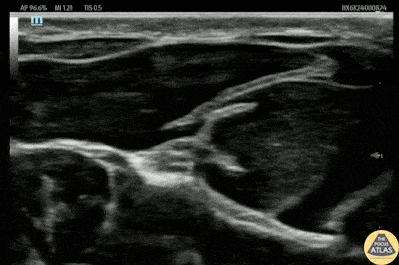

30s M presented with a laceration to his thenar eminence. He was neurovascularly intact, and there was no concern for retained foreign body or fracture. To facilitate laceration repair, a median nerve block was performed. Shown here, the median nerve is seen in the fascial plane between the muscle bellies of the flexor digitorum superficialis and flexor digitorum profundus. A 27g needle was advanced using in-plane guidance into the fascial plane, and after a negative aspiration for blood, anesthetic was injected, with spread of anesthetic visualized surrounding the median nerve. The patient had significant improvement in his pain, and the laceration was able to be irrigated and repaired. Dr. Michael Heffler, Fellow Denver Health Ultrasound Fellowship